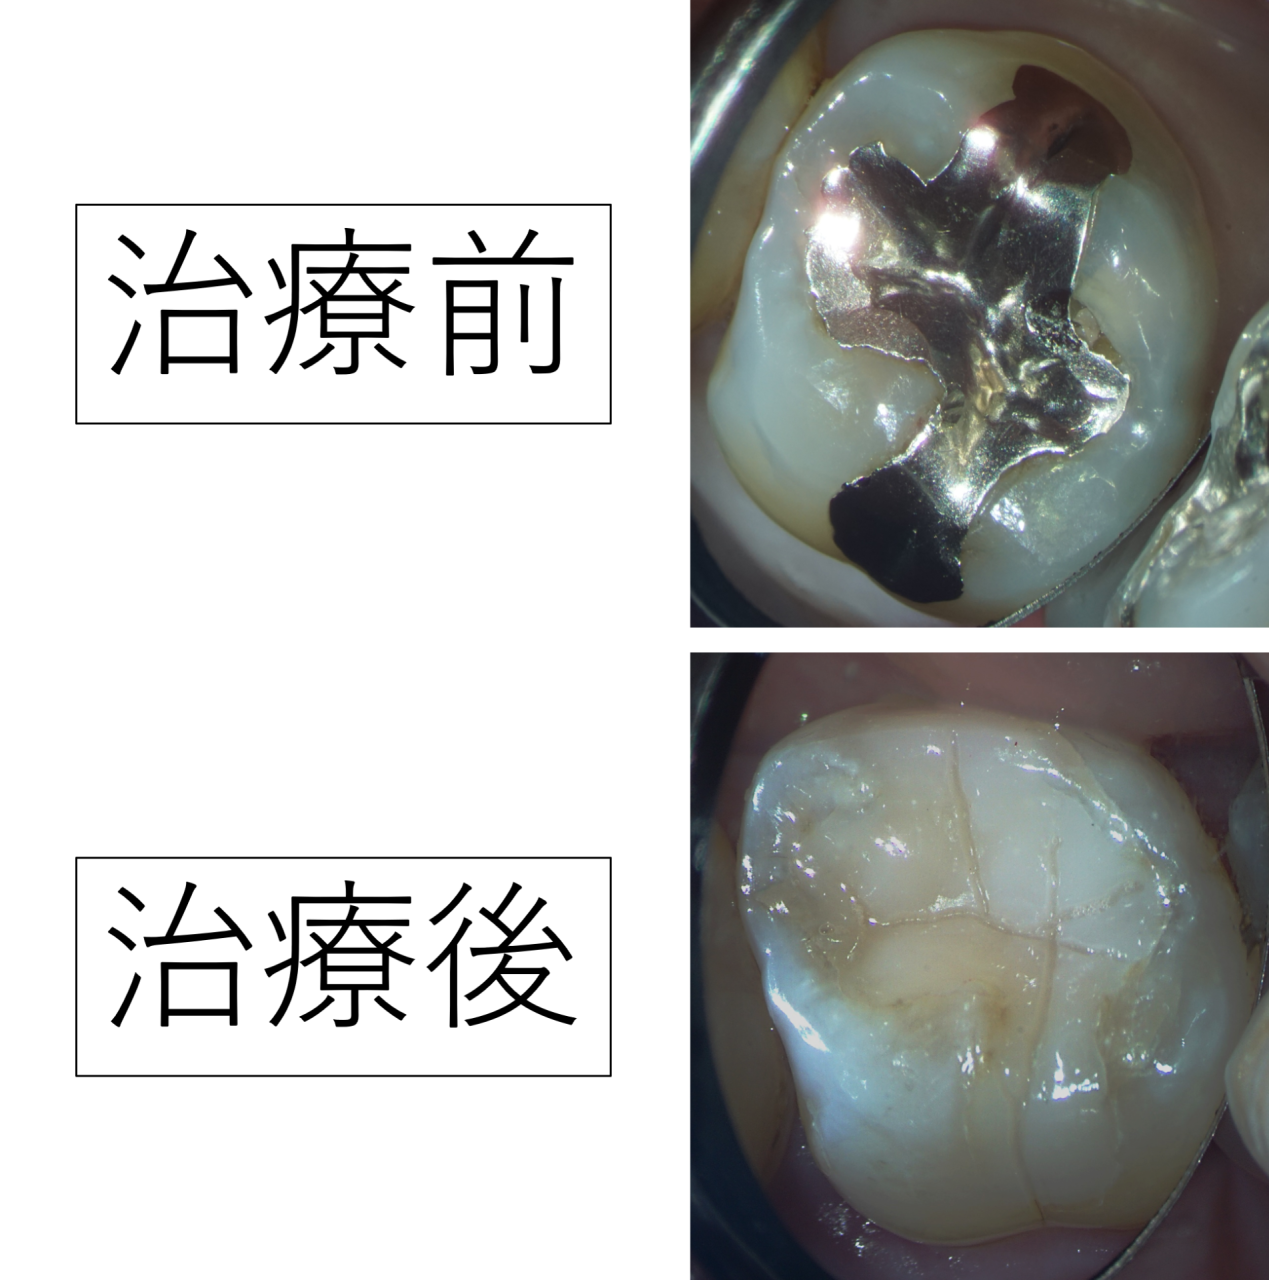

今回の症例では、銀歯の歯が噛んだ時や冷たい物を飲んだ時に痛いとのことでした。

歯を診査すると、銀歯と歯の間にすき間があり、虫歯の穴が開いています。硬い銀歯で歯がかけて、そこに虫歯菌が入って虫歯ができたものと考えられます。

銀歯を外してみたところ、二次う蝕(詰め物の下で再発した虫歯)が確認できました。外からは分かりにくく、つめ物を外して初めて歯の状態がはっきりすることもあります。

今回のケースでは、再発した虫歯を丁寧に取り除いたあと、レジン(プラスチック樹脂)による修復を行いました。

レジンは白く歯の色に近く、修復後に自然になじみやすい材料です。

治療後は噛んだ時の痛みやしみる感じは無くなったそうで、患者様は喜ばれました。本当に良かったです。